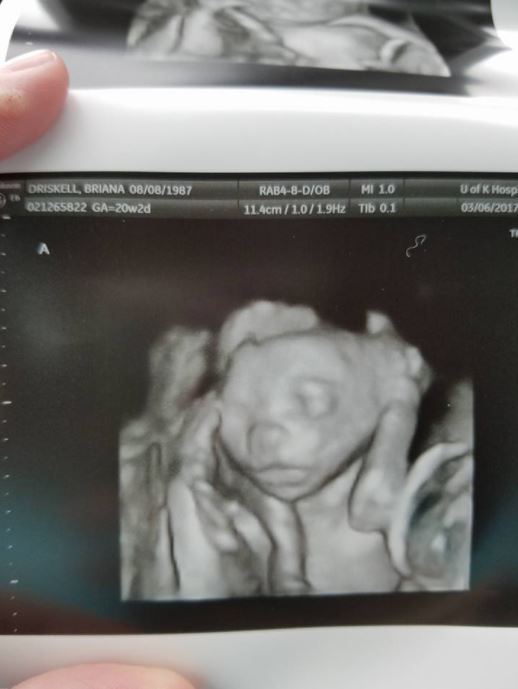

然而,當懷孕8週的布萊安娜到醫院進行產檢時,醫生卻給了他們更大的驚喜!

透過超音波畫面可以看到,布萊安娜肚子裡竟然出現五個胎兒!

之前一直不懷孕,沒想到一來就是五個,戲劇性的變化讓她相當震撼「我是真的差點昏 倒!」

「我當時震 驚到說不出話,就做在那裡呆瞪著螢幕,完全不敢相信。我真的不知道我可以一次懷上五個寶寶。」